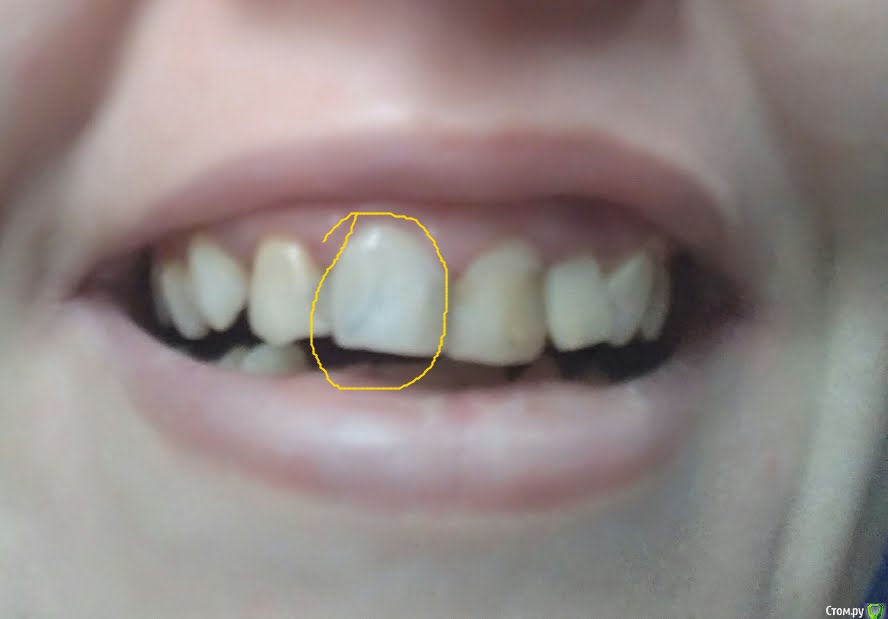

ya2mama Опубликовано 30 марта, 2018 Поделиться Опубликовано 30 марта, 2018 (изменено) Здравствуйте! Установили мне сегодня светопломбу, а результат не идеален. Фото прикрепила (лучшего качества сделать не могу, добавлю только что темные линии на самом деле видны гораздо отчетливее). Врач говорит, что после лечения ВСЕХ зубов можно будет сделать полировку и тогда факт реставрации будет незаметен. Действительно ли полировка поправит внешний вид запломбированного зуба? И почему эта процедура не может быть проведена сразу? Изменено 30 марта, 2018 пользователем ya2mama Ссылка на комментарий

ya2mama Опубликовано 30 марта, 2018 Автор Поделиться Опубликовано 30 марта, 2018 (изменено) Пломбы стоят с обеих сторон указанного зуба, обе сегодняшние. И такая неоднородность цвета Изменено 30 марта, 2018 пользователем ya2mama Ссылка на комментарий

dok1 Опубликовано 30 марта, 2018 Поделиться Опубликовано 30 марта, 2018 Все 4 резца имеет смысл покрыть коронками всилу большого объёма пломбировачного материала, восстанавливающего зубы с нескольких поверхностей. Идеальные в эстетическом плане реставрации пломбировочным материалом сделать можно. Это стоит, обычно, дороже простой пломбы. Но в вашем случае неоправданно. В искомом зубе канал запломбирован хорошо. При правильной обработке канала перед пломбированием разряжение уйдёт. 3 Ссылка на комментарий